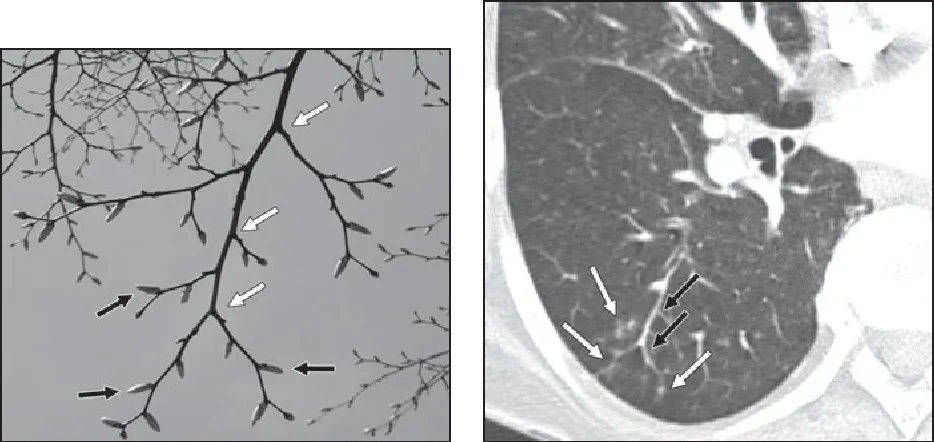

3) endobronchial spread

•

경계가 분명한 2~4 mm 크기의 nodules 또는 branching

Tree-in-bud sign : 의미. 흔함.